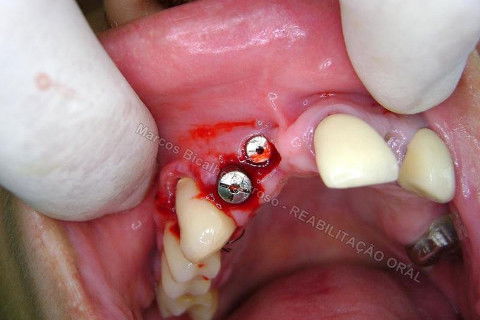

Iniciei esta etapa com o uso de um bisturi circular para contra ângulo. Na verdade, estou postando novamente este procedimento, mas realmente, cheguei depois a conclusão que não deveria ter agido assim nos dentes anteriores, onde a estética é primordial, não devemos remover tecido mole, mas manipular para promover um aumento de papila. Este bisturi é útil para dentes posteriores, adianta bastante o trabalho, é rápido, remove uma porção do formato e dimensão da plataforma do implante, a conta para adaptação do cicatrizador.

Reparem no corte...bonitinho mas fiquei com raiva depois. rsrsrs. Caramba, por que que eu tinha que tirar esta gengiva dali? Era só enrolar o excesso para a vestibular e conseguiria um bom aumento de volume gengival, o que ajudaria bastante na estética periimplantar. Mas tudo bem, vou fazer a cirurgia periodontal depois para corrigir isto sem cobrar da paciente, só de raiva. hehehe. Tem que rir para não chorar.

Aqui até que tudo bem, mas nos anteriores, não podia.